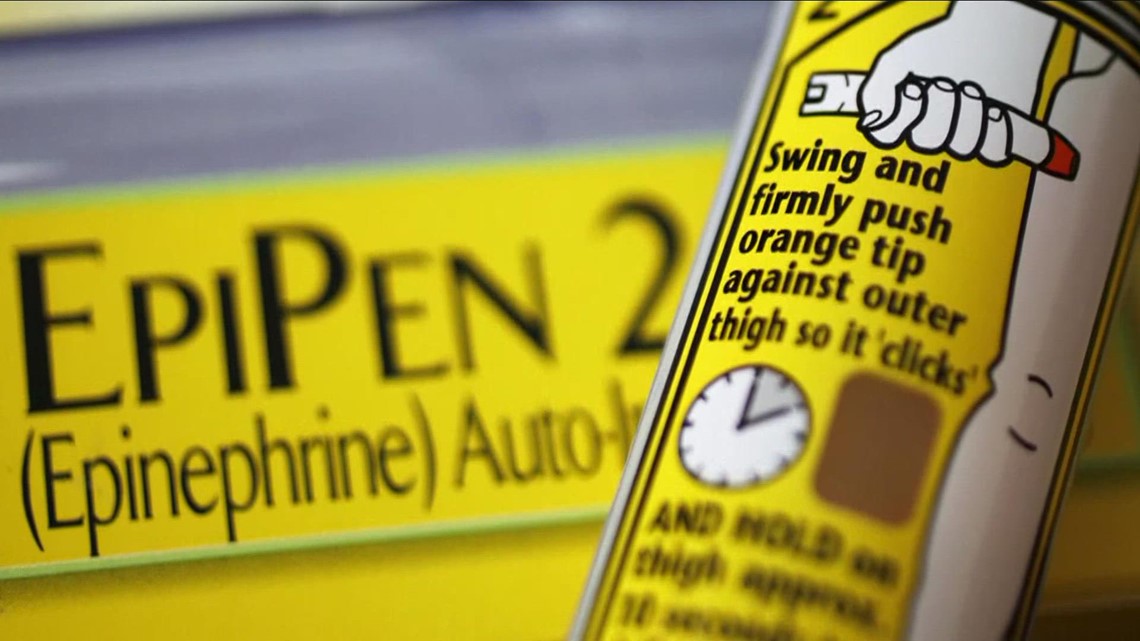

What is an EpiPen?

EpiPen is the name brand for an epinephrine autoinjector. Epinephrine is another term for “adrenaline.” EpiPens are used when someone is having a severe allergic reaction. Children with allergies often bring them to school, and adults with severe allergies often keep them nearby.

The “pen” is a vial of adrenaline attached to a spring loaded needle. When the device is pressed against the thigh (where EpiPens are generally used), the spring loaded needle is triggered, injecting the patient with the adrenaline.